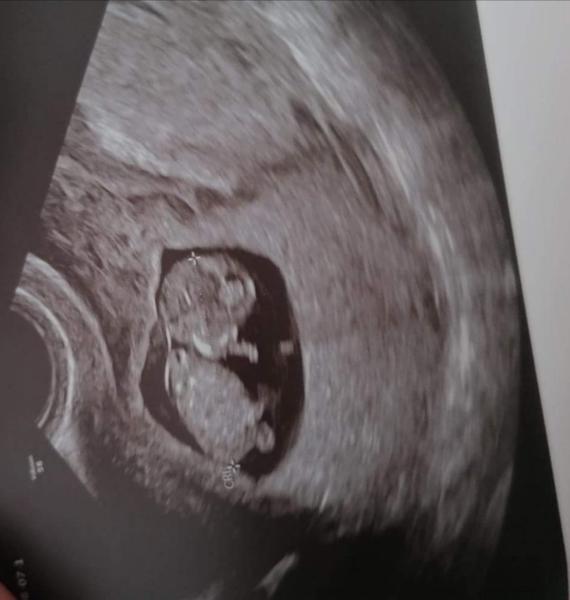

Dobrý deň, chcela by som sa len spýtať, či mala niektorá z Vás odlúčenie bábätka (nechcem to nazvať ešte placentou keďže zatiaľ je to gestacny vak) v 1 trimestri tehotenstva. Ak áno ako to dopadlo? Za každú skúsenosť vopred ďakujem. Som 11+2.

@olivia1425 no väčšinou sa stáva že sa odlučuje placenta už.. Len že keďže som ešte v 11tt+3 tak to ešte placenta nie je ale tuším gestačný vak.. No a bábätko nie je úplne na stene maternici ale je odlúčené kus.. Skrz tej zrazeniny krvy ktorá sa ešte nevstrebala alebo nevytiekla.